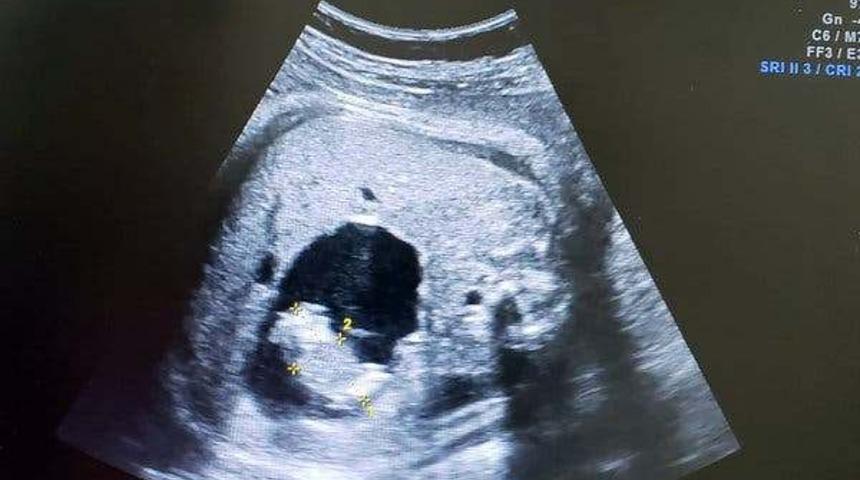

Kolombiya, Barranquilla’da yaşayan Monica Vega’nın doktorları doğumdan iki ay önce yaptıkları kontrol sırasında ultrasonda iki göbek kordonu olduğunu gördüler. Bu durumun nedeni Vega'nın ikiz bebeklere hamile olması değildi. Vega’nın beklediği kız bebek rahimdeki diğer fetüsü emmiş ve daha sonra ona göbek kordonu ile bağlanmıştı.

Bu nedenle de Vega’nın doktorları paraziter ikizin büyüyüp gelişmekte olan bebeğin organlarına zarar vereceğinden endişelendikleri için Vega’yı hemen ameliyata aldı. Vega, Itzmara ismini koyduğu kız çocuğunu dünyaya getirdi. Daha sonra ise Itzmara ameliyata alınarak içerisinden paraziter ikizi çıkarıldı. Kalbi veya beyni olmayan paraziter ikiz, yalnızca Itzmara’dan beslendiği için o süreçte hayatta kalmıştı.

Tıpta “Fetüs içinde fetüs” olarak adlandırılan bu durum, şu ana kadar yaklaşık 200 kişide görüldü. Ulusal Sağlık Enstitüleri tarafından yayınlanan 2010 raporuna göre “Fetüs içinde fetüs” durumu her 500 bin doğumdan sadece birinde meydana geliyor. Oldukça nadir olarak görülen ve bir çeşit gelişimsel anormallik olarak açıklanabilen bu durum, ikiz bebeklerden birinin büyümeyi durdurması sonucunda da yaşanabiliyor.

İkiz bebeklerden biri gebelik sırasında büyümeyi durdurduğunda, fiziksel olarak tamamen gelişmekte olan diğer ikize bağlanıyor. Bu durum ultrasonda çok nadir olarak fark ediliyor. Genellikle doğum esnasında fetüs içinde fetüs vakaları tespit edilebiliyor. Ancak, bunun gözden kaçtığı ve ikizlerin yıllarca içlerinde bir paraziterle yaşadıkları durumlar da olabiliyor. Geçtiğimiz yıllarda da Hindistan’da benzer bir vakaya rastlanmıştı.